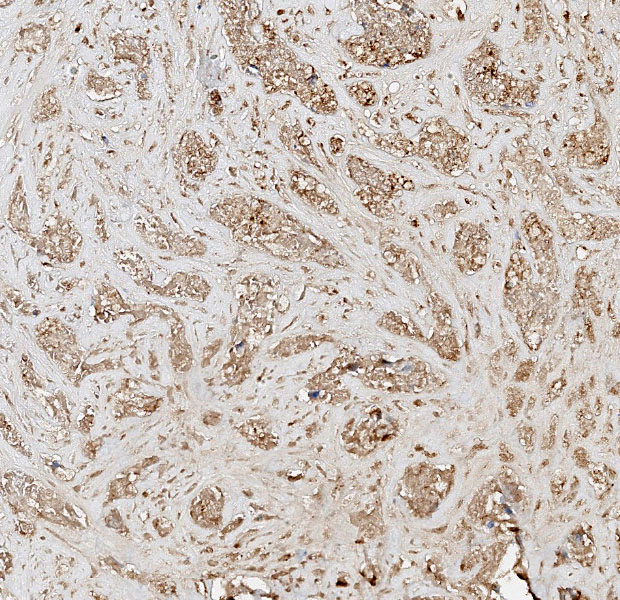

Differential diagnoses for this urinary bladder mass included urothelial cell carcinoma, prostatic carcinoma, and renal carcinoma, with the latter two included largely to ensure that metastatic or locally invasive disease was not being overlooked. The histologic architecture of an infiltrative epithelial neoplasm seemingly arising from the bladder wall favored a urothelial origin, but immunohistochemistry provided an additional layer of information. The neoplastic cells were diffusely immunoreactive for CK7, a cytokeratin expressed in most primary urinary bladder carcinomas.4 They were negative for GATA3, a transcription factor involved in urothelial differentiation, which may suggest prostatic carcinoma instead.5 However, Dr. Alves noted that GATA3 is most reliable in well-differentiated urothelial carcinomas, and its absence here is also consistent with less well-differentiated UCCs, as in this case.5 The tumor was also negative for PAX8, a marker of renal tubular epithelium, which helped exclude renal carcinoma.2 Uroplakin, a highly specific marker for urothelial cell carcinoma, unfortunately did not work in this case.7 Participants also discussed the glandular differentiation present within the tumor, which can be seen in both urothelial cell and prostatic carcinomas. In humans, glandular differentiation in urothelial carcinoma is associated with invasion and poorer differentiation.8 While extrapolating across species is something to be avoided, the same pattern was evident here.